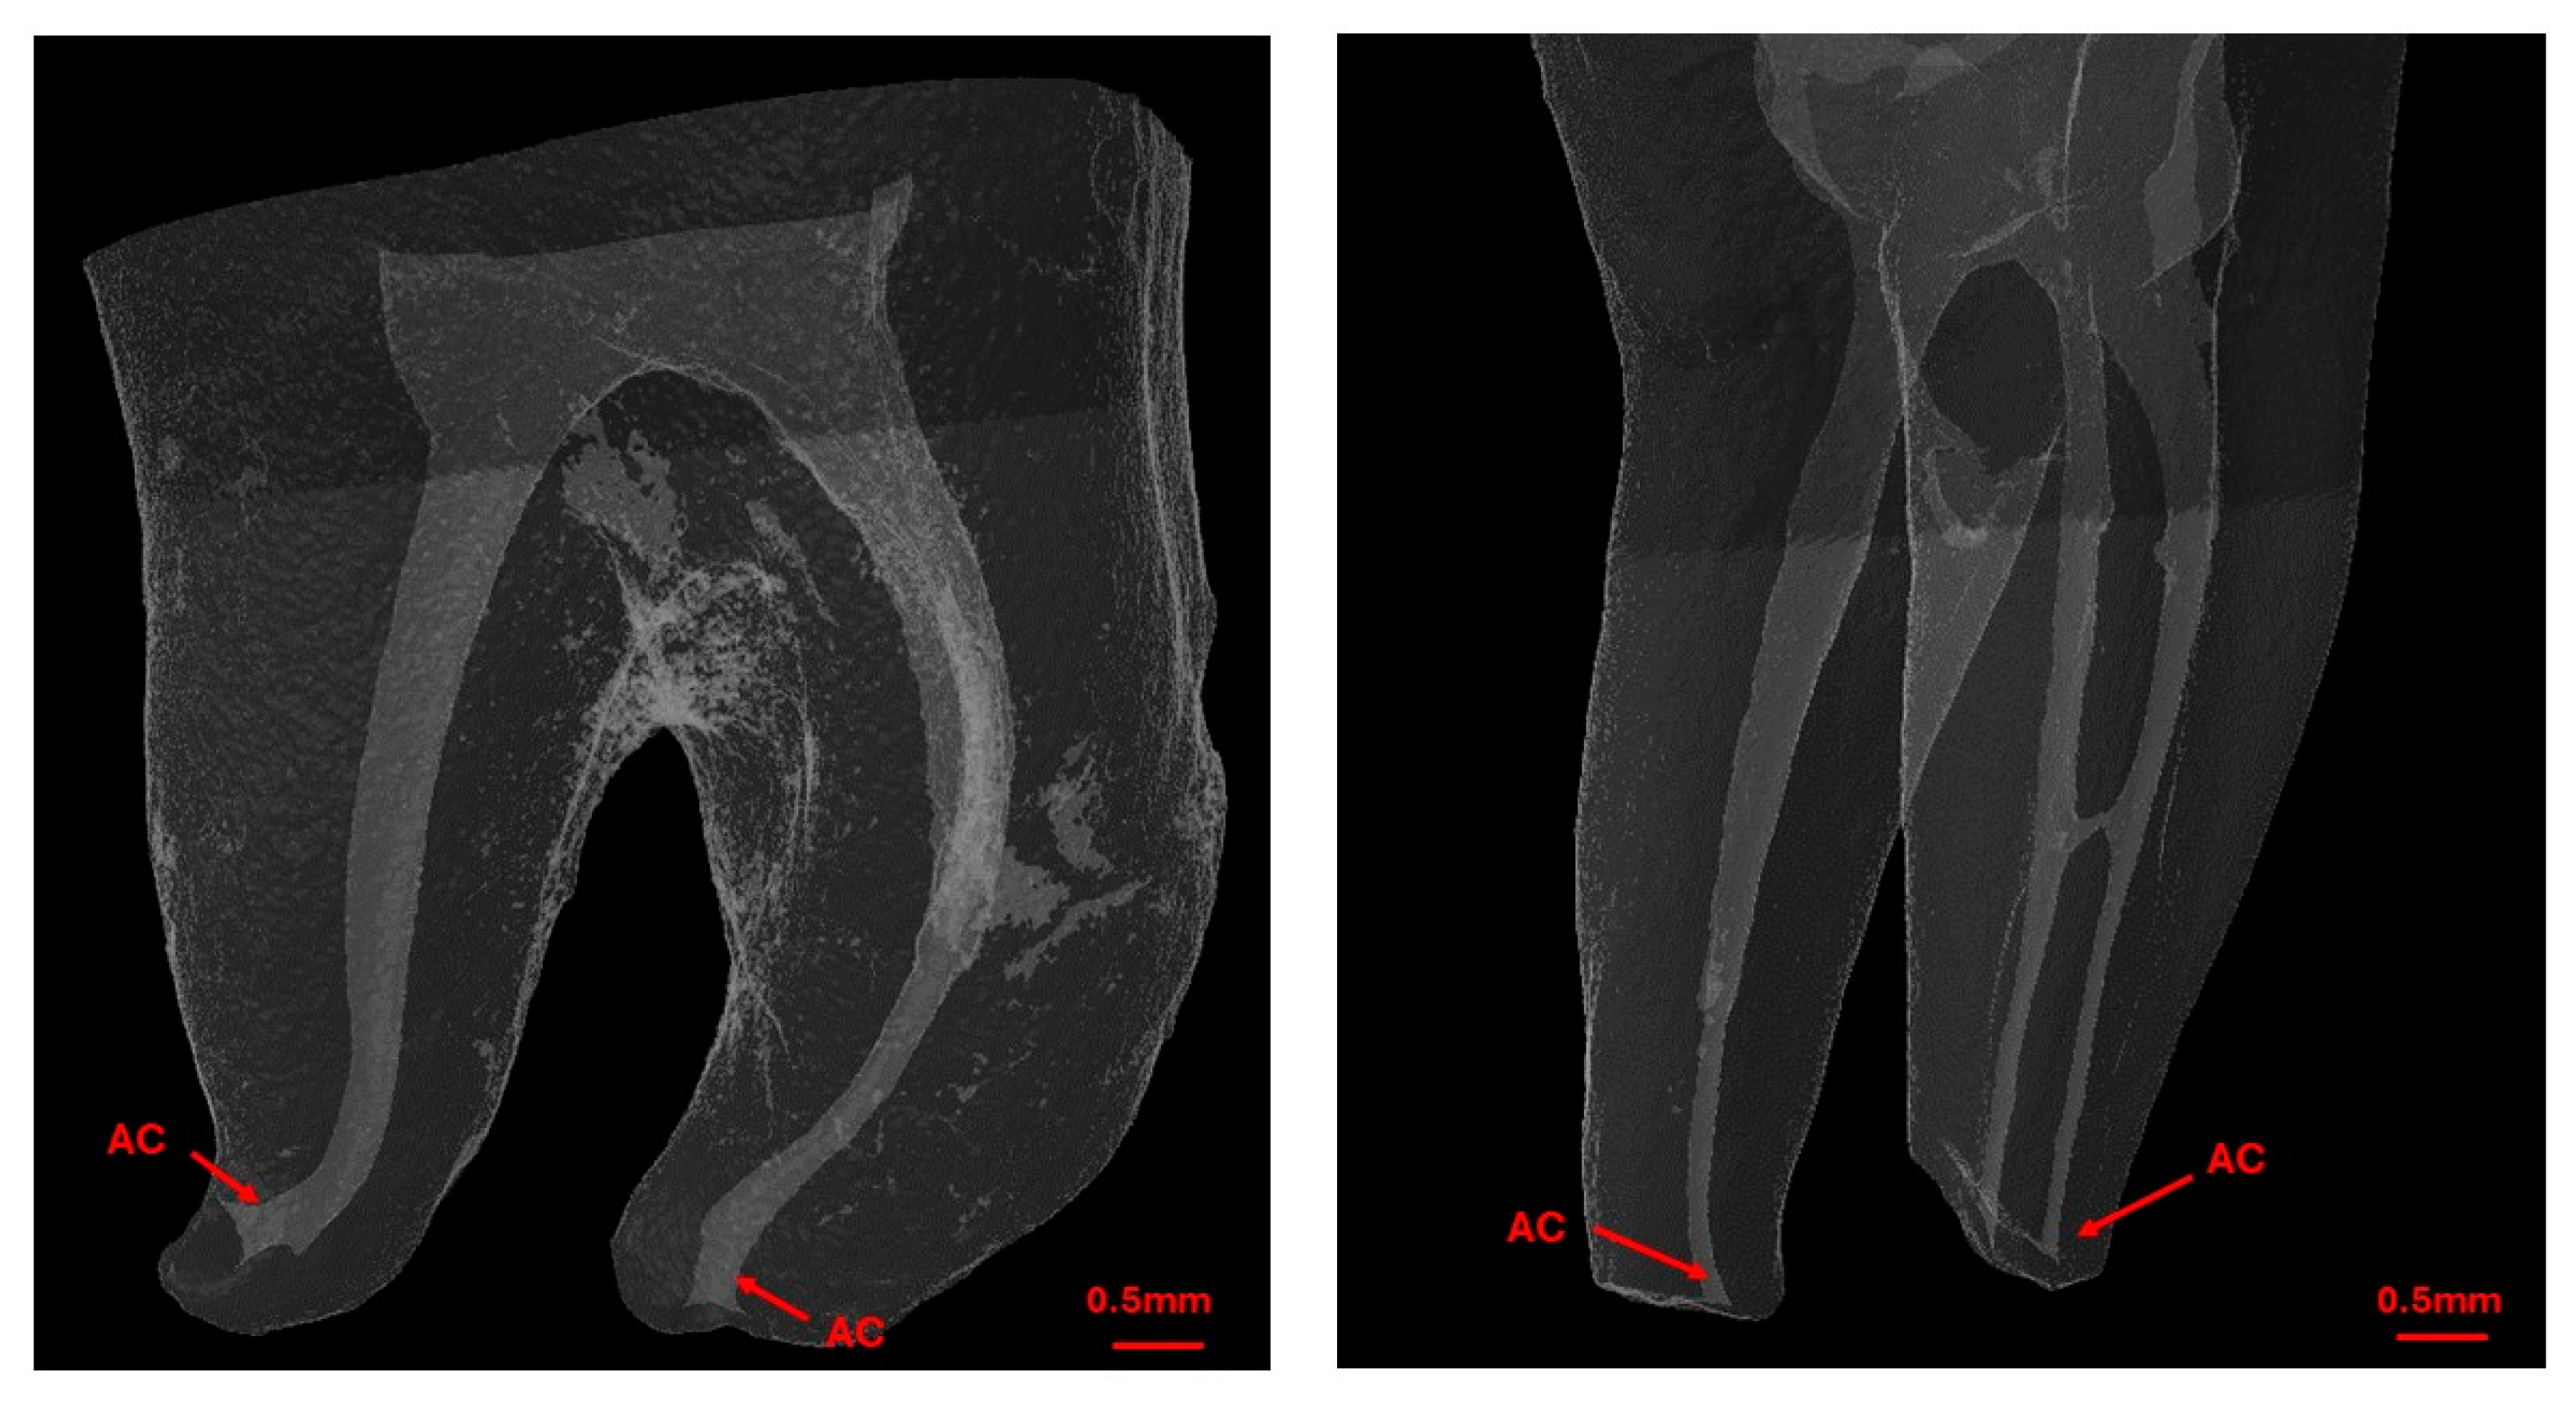

Prior to determining the WL of root canals, the first scan captured detailed anatomical data. A single operator identified the apical constriction (AC) as the most apical zone with the smallest cross-sectional area that extends at least 0.1 mm (Figure 3). The most apical position of the AC was marked and used as a reference point for the subsequent EAL measurements. During this scan, the distance between the AC and major foramen (AF) was recorded for each canal.

Figure 3.

Micro-CT reconstructions of the tooth showing the external and internal anatomy of the root canal system with AC highlighting the position of the apical constriction.